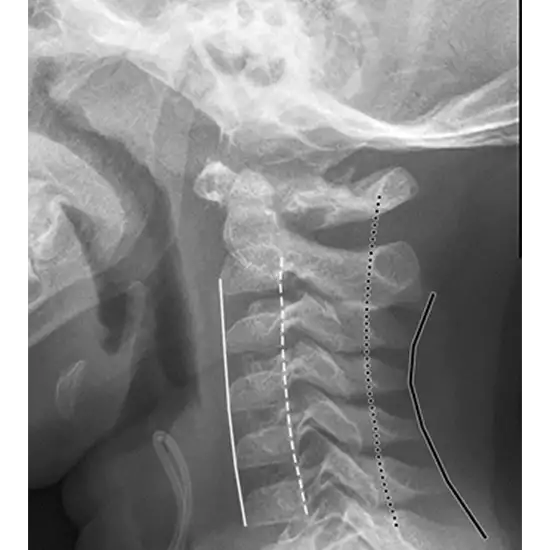

What is an X-ray Cervical Dorsal Test?

An X-ray of the dorsal spine (thoracic spine) visualizes the twelve thoracic vertebrae (T1-T12) that make up your central backbone. Additionally, it is beneficial to visualize their intervertebral discs and the surrounding soft tissues, such as skin and muscles.